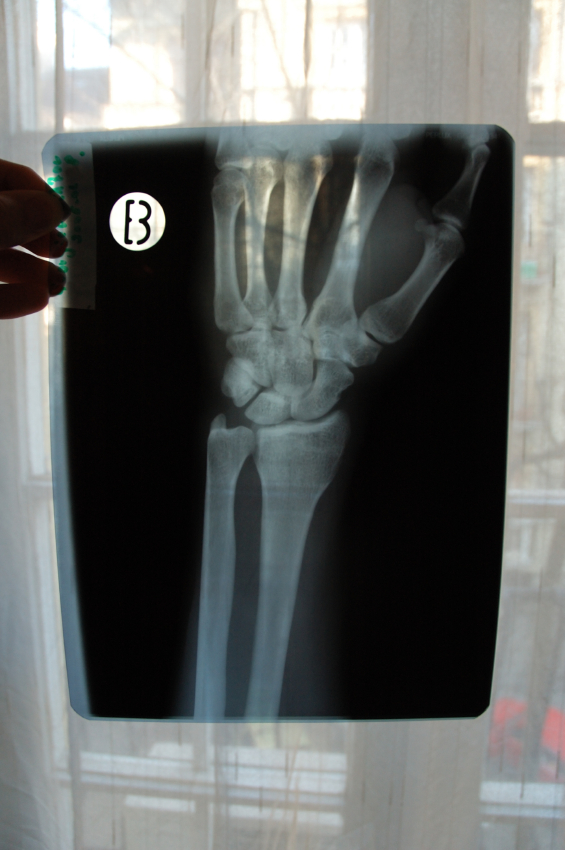

W badaniu ultrasonograficznym (usg) stawów nadgarstkowych zostaje uwidoczniony nerw pośrodkowy (NP). O zespole cieśni nadgarstka (ZCN)może świadczyć zwiększone pole przekroju NP (obrzęk nerwu) oraz wzmożony sygnał w opcji power doppler (przekrwienie). Jedną z przyczyn ograniczonego znaczenia usg w diagnozowaniu ZCN jest brak dokładnego ustalenia granicznej wartości pola przekroju NP oraz miejsca wykonywania tego pomiaru.

Badacze z Austrii przeprowadzili badanie usg u 135 chorych z podejrzeniem ZCN. Ostateczną diagnozę potwierdzono na podstawie badania klinicznego oraz elektrofizjologicznego. Przekrój NP był mierzony w 5 różnych miejscach anatomicznych w zakresie przedramienia oraz kanału nadgarstka, ponadto wyliczano różnicę i iloraz dokonanych pomiarów NP na przedramieniu i w kanale nadgarstka aby wyeliminować wpływ zmienności osobniczej przekroju NP .

ZCN zdiagnozowano w 111 badanych nadgarstkach (45,5%), wykluczono w 49 nadgarstkach (34,4%) w 49 nadgarstkach stwierdzono prawdopodopodobne występowania ZCN. Ustalono wartości progowe przekroju NP 9,8-13,8mm2, dla których czułość i specyficzność w diagnostyce ZCN wynosiła 92%. Wzmożony sygnał w opcji Power Doppler (określany jako stopień 2 lub wyższy) wskazywał na rozpoznanie ZCN ze specyficznością 90%. W przeprowadzonym eksperymencie nie wykazano przewagi określonego punktu dokonywania pomiaru pola przekroju NP. Autorzy badania zalecają w praktyce klinicznej dokonywanie pomiaru NP w kanale nadgarstka pod troczkiem zginaczy w miejscu gdzie pole przekroju jest największe.